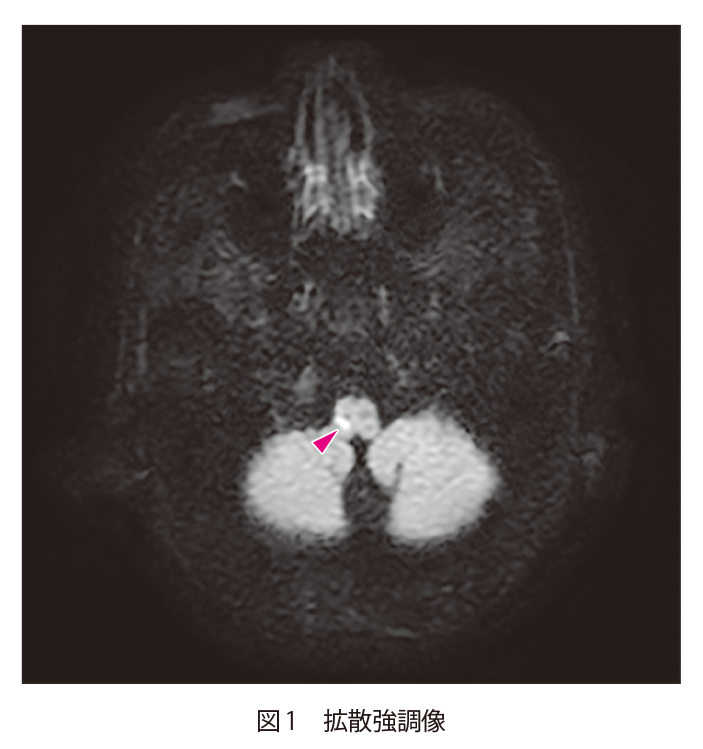

頭痛と歩行障害で救急受診した70歳代男性 70歳代男性,頭痛で近医受診.頭部CTでは異常なしと診断された.翌日より歩行困難と嘔吐が生じたため救急受診し,頭部CTが施行された. A1.椎骨動脈解離による延髄外側梗塞A2.脳外科へのコンサルト 1.診断のポイント 延髄右側に拡散強調像高信号がみられ(図1▶︎)ADC値も低下している(非呈示).急性期梗塞の所見である.MRAでは右の椎骨動脈が全く描出されていないが(図2▶︎),FLAIRでは淡い高信号として描出されており,内部に低信号域がみられる(図3▶︎).同日のCT血管造影では右椎骨動脈は動脈相で淡い造影効果を呈し,内部にflap状の構造がみられる(図4▷).右椎骨動脈解離による延髄梗塞である. 2.鑑別診断1) 延髄に病変をきたすものが鑑別となりうる. 1 梗塞 椎骨動脈解離によらないラクナ梗塞,アテローム血栓性梗塞で延髄梗塞をきたす.アテローム血栓性梗塞は延髄外側よりも内側に起こりやすい. 2 腫瘍 毛様細胞性星細胞腫,血管芽腫や,低悪性度の神経膠腫,神経膠芽腫などが鑑別にあがるが,低悪性度の神経膠腫以外は頻度も少なく,経過も異なる. 3 感染・炎症性疾患 小さな膿瘍が梗塞と紛らわしい場合があるが,稀である.感染性脳炎としてHIV患者におけるサイトメガロウイルス感染,単純ヘルペスウイルス感染で延髄単独病変の報告がある.またADEM(acute disseminated encephalomyelitis:急性散在性脳脊髄炎)が片側性に延髄病変をきたす場合がある.しかし,これらの経過や症状は延髄梗塞とは異なる. 4 脱髄疾患・代謝性疾患など 視神経脊髄炎関連疾患,多発性硬化症の延髄病変が片側性に出現する場合がある.Sjögren症候群,Behçet病,サルコイドーシスも片側に出現する場合がある.ただしこれらも経過や症状は延髄梗塞とは異なると思われる. 5 その他 PRES(posterior reversible encephalopathy syndrome:可逆性後頭葉白質脳症)やAVF(arteriovenous fistula:動静脈瘻)で延髄に病変をきたす場合がある.また,肥大性オリーブ核変性症など類似の画像を呈する. 3.次の一手 脳外科にコンサルトを行う.画像的にはMRI撮像時に3Dグラディエント造影T1強調像が撮像できれば血管内膜のflapや解離腔自体の描出が可能であるが,病歴などから解離や梗塞を疑わなければ咄嗟に判断して造影するのは難しいかもしれない.延髄を含む後方循環系の梗塞は内頸動脈領域の梗塞と比較して発症早期での拡散強調像での偽陰性率が高く2),延髄では24時間以内での偽陰性率が高いとの報告があるため、発症早期に拡散強調像高信号が見られなくても超急性期の延髄梗塞を除外できないので注意しなければならない3,4). 救急医Check Point 脳動脈解離は,欧米では頭蓋外内頸動脈に多く,本邦では頭蓋内椎骨動脈に多い.40〜50歳代の比較的若年者に発生する.最も頻度の高い症状は頭痛,頸部痛で70〜80 %に認められ,椎骨動脈解離では後頭部や項部に限局した痛みがみられる.頭痛の特徴としては,はじめての痛み,顔面痛あるいは頸部痛,片側性,持続性(1カ月以内に寛解)などで,解離に伴う痛みであるにもかかわらず必ずしも突然ではなく緩徐に発症することも多い.頭痛の性状は多岐にわたり日常生活に支障がない程度の場合もあるため,性状のみで一般的な頭痛と区別することは困難である.首を鳴らす,急激に振り向くなどの頸部の回転動作の後に頭痛,頸部痛が発生した場合は椎骨動脈解離を疑うきっかけとなる. 発症様式は「虚血(脳梗塞,TIA)」「出血(くも膜下出血)」「無症状もしくは頭痛のみ」の3型となり,出血の有無が患者の予後を最も左右する.本症例を疑った場合は脳神経外科医への紹介が必須だが,「虚血」「出血」発症を疑った場合は可及的すみやかに外科的治療(血管内治療含め)を検討する必要がある.病理所見により確定診断となるが,実臨床においては画像検査(脳血管造影,CT,MRI)にて診断される.まずCTにて「虚血」「出血」の有無を評価し,その後はCTA,血管造影,MRI(MRA,BPAS)で詳細な評価をしていく.遠位の虚血のほとんどは,解離部位の部分的な狭窄や閉塞による低灌流によってではなく,解離部位から放出された塞栓によって起こる.「虚血」「無症状もしくは頭痛のみ」発症の場合は初回の画像検査での診断が困難なことが多いが,発症から3週間程度の間に患部に形態変化を生じることがよくあるため,発症時の症状(頭痛)で疑い,臨床経過,画像経過をフォローすることが重要である. 引用文献 Prakkamakul S, et al:MRI Patterns of Isolated Lesions in the Medulla Oblongata. J Neuroimaging, 27:135-143, 2017 Oppenheim C, et al:False-negative Diffusion-Weighted MR Findings in Acute Ischemic Stroke. AJNR Am J Neuroradiol, 21:1434-1440, 2000 Seo MJ, et al:Diffusion Weighted Imaging Findings in the Acute Lateral Medullary Infarction. J Clin Neurol, 2:107-112, 2006 Kitis O, et al:Wallenberg’s Lateral Medullary Syndrome:Diffusion-Weighted Imaging Findings. Acta Radiol, 45:78-84, 2004 参考文献 「ここまでわかる頭部救急のCT・MRI」(井田正博/著),メディカル・サイエンス・インターナショナル,2013 (2020/5/1公開) 戻る この"ドリル"の掲載書をご紹介します レジデントノート増刊 Vol.22 No.2画像診断ドリル救急医と放射線科医が伝授する適切なオーダーと読影法 藪田 実,篠塚 健/編 定価:4,700円+税 在庫:あり 月刊レジデントノート 最新号 次号案内 バックナンバー 連載一覧 定期購読案内 定期購読WEB版サービス 定期購読申込状況 レジデントノート増刊 最新号 次号案内 バックナンバー 定期購読案内 residentnote @Yodosha_RN その他の羊土社のページ ウェブGノート 実験医学online 教科書・サブテキスト 広告出稿をお考えの方へ 広告出稿の案内